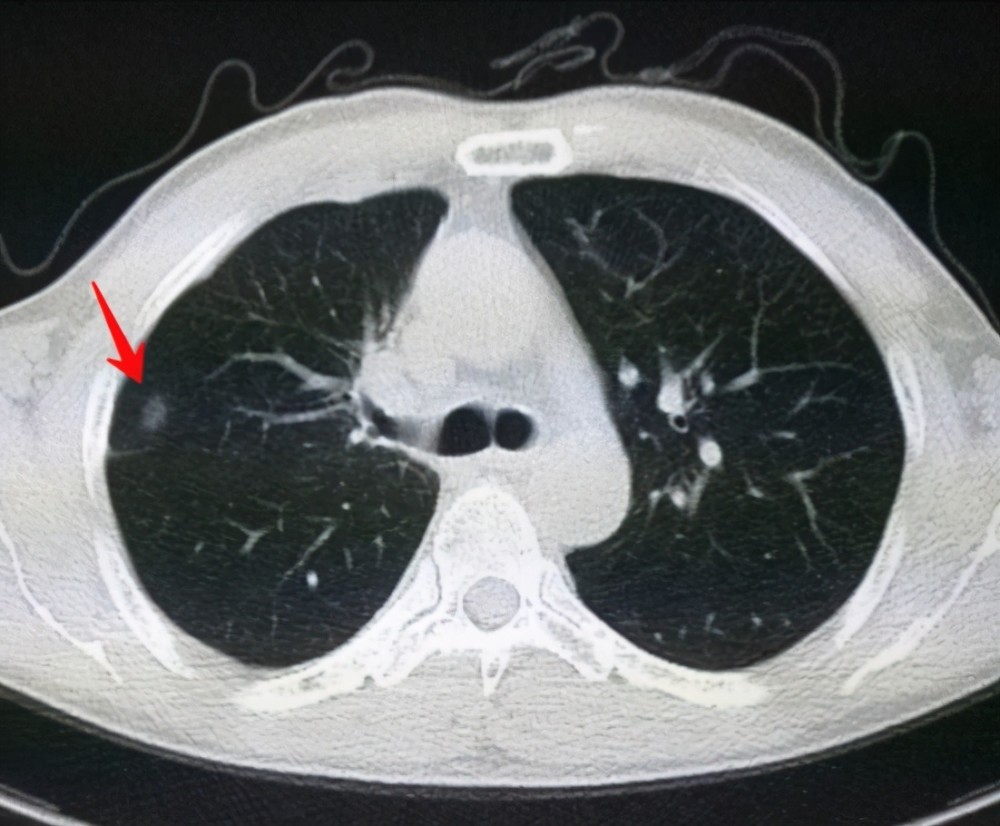

肺結(jié)節(jié)是一種常見(jiàn)的肺部疾病,其發(fā)病率逐年上升,雖然肺結(jié)節(jié)多數(shù)情況下是良性的,但也有可能惡化為肺癌,了解肺結(jié)節(jié)的形成原因?qū)τ陬A(yù)防和治療具有重要意義,本文將為您詳細(xì)解析肺結(jié)節(jié)的形成機(jī)制。